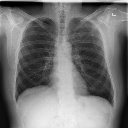

Arrastra y suelta una imagen de radiografía de tórax (formato JPG o PNG) en el área de carga, o haz clic en 'Elegir Archivo' para explorar tu computadora. También puedes probar una de nuestras imágenes de muestra.

El sistema mostrará puntuaciones de probabilidad para cuatro condiciones: Tuberculosis, Neumonía, COVID-19 y Normal. Cada resultado muestra un porcentaje y nivel de riesgo.

Los indicadores verdes muestran bajo riesgo (menos del 50%), mientras que los indicadores rojos muestran alto riesgo (50% o más). Para la clasificación Normal, porcentajes más altos indican pulmones más saludables.